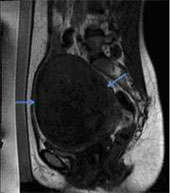

Transabdominal USG performed showed a 7.9 x 7.4 cm sized anterior myometrial fibroid. MRI showed a hypointense fibroid on T2 weighted images measuring 11.5(TR) x 11.5(SI) x 9.1(AP) cm (Fig. 1).

Fig. 1 – T2 weighted sagittal image showing a large fundal hypointense fibroid (blue arrows), with a central area of hyperintensity, representing internal degeneration (red arrows).